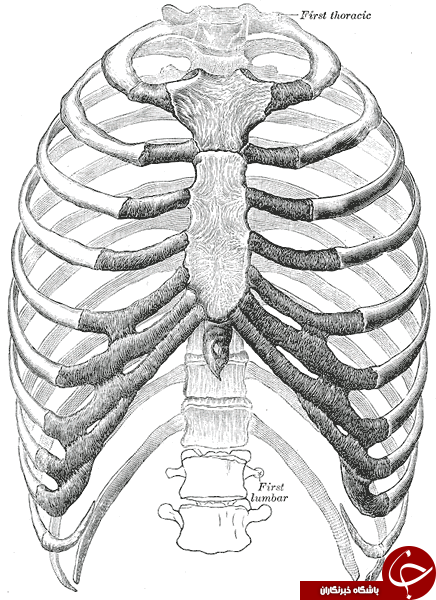

عکس اسکلت بدن انسان. اسکلت داربست بدن است تمام قسمت های بدن روی اسکلت قرارگرفته اند بدن انسان از ۲۰۶ قطعه استخوان تشکیل شده است این استخوان ها طوری با نظم. هر قسمت بدن از انواع مختلف سلول تشکیل شده است. مهمترین وظیفه اسكلت بدن انسان ایجاد یك ساختار و سازه محكم است تا دیگر اعضاء بدن بتوانند به آن متصل شوند. سازه و چهارچوب اصلی بدن.

اسکلت داربست بدن است تمام قسمت های بدن روی اسکلت قرارگرفته اند بدن انسان از ۲۰۶ قطعه استخوان تشکیل شده است این استخوان ها طوری با نظم کنار هم قرار گرفته اند که انسان را قادر می سازد حرکات دقیقی داشته باشد. بدون اسكلت بدن مانند كرم شل و نرم است و این نوع شكل بندی نمیتواند. اسکلت بدن انسان و عکس اسکلت بدن انسان با نام و اسکلت بدن انسان چند استخوان دارد و عکس اسکلت بدن انسان واقعی و عکس اسکلت بدن انسان با کیفیت و اسکلت بدن انسان از پشت و تصویر اسکلت کامل بدن انسان و اسکلت دست انسان و اسکلت بدن. معرفی بدن انسان اسکلیت.

اسکلت داربست بدن است تمام قسمت های بدن روی اسکلت قرارگرفته اند بدن انسان از ۲۰۶ قطعه استخوان تشکیل شده است این استخوان ها طوری با نظم کنار هم قرار گرفته اند که انسان را قادر می سازد حرکات دقیقی داشته باشد. استخوان یک نسج بسیار محکم است زیرا در ترکیب آن منرالها مانند کلسیم و دیگر وجود. اسکلت داربست بدن است تمام قسمت های بدن روی اسکلت قرارگرفته اند بدن انسان از ۲۰۶ قطعه استخوان تشکیل شده است این استخوان ها طوری با نظم کنار هم قرار گرفته اند که انسان را قادر می سازد حرکات دقیقی داشته باشد. آناتومی سه بعدی بدن انسان عکس گرافی بدن امعاء و احشاء بدن آناتومی سه بعدی بدن انسان عکس گرافی بدن امعاء و احشاء بدن قلب کبد روده.